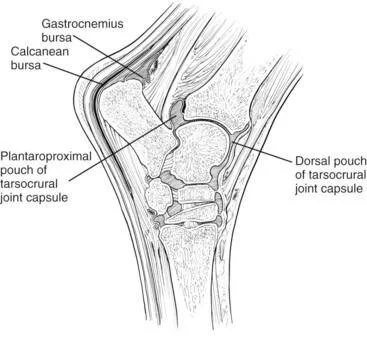

Diagnosis of this condition was confirmed by scanning the iliac arteries using transrectal ultrasound imaging. Normally the arteries are wide and uniform in cross section and the blood flow can be clearly seen. In the ultrasound images below, the dense grey structure within the vessel is the thrombus. The colour image is achieved using doppler to capture the blood flow and shows how the thrombus is partially occluding the artery.

A large thrombus within the iliac artery

This horse actually had a thrombus in the left and right iliac artery which is very unusual.

There is a surgical treatment option to try and remove the thrombus, however it is a risky procedure and recurrence is a possibility. In this case the horse was retired to pasture as a companion animal.